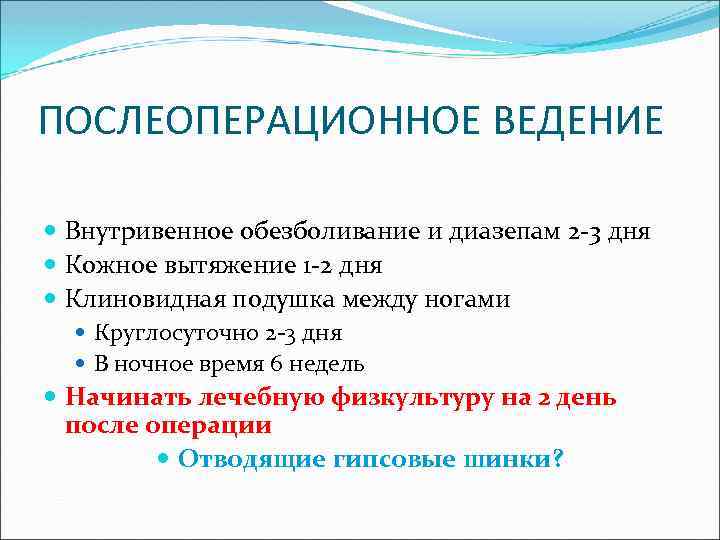

ПОСЛЕОПЕРАЦИОННОЕ ВЕДЕНИЕ Внутривенное обезболивание и диазепам 2 -3 дня Кожное вытяжение 1 -2 дня Клиновидная подушка между ногами Круглосуточно 2 -3 дня В ночное время 6 недель Начинать лечебную физкультуру на 2 день после операции Отводящие гипсовые шинки?